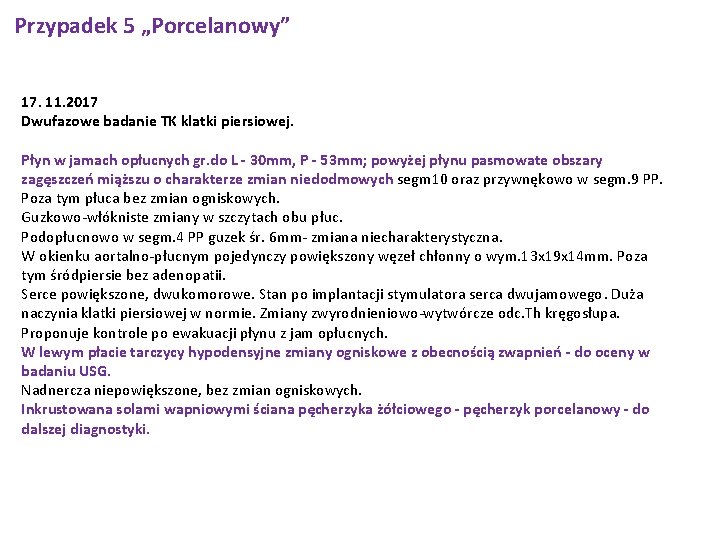

Przypadek 5 „Porcelanowy” 17. 11. 2017 Dwufazowe badanie TK klatki piersiowej. Płyn w jamach opłucnych gr. do L - 30 mm, P - 53 mm; powyżej płynu pasmowate obszary zagęszczeń miąższu o charakterze zmian niedodmowych segm 10 oraz przywnękowo w segm. 9 PP. Poza tym płuca bez zmian ogniskowych. Guzkowo-włókniste zmiany w szczytach obu płuc. Podopłucnowo w segm. 4 PP guzek śr. 6 mm- zmiana niecharakterystyczna. W okienku aortalno-płucnym pojedynczy powiększony węzeł chłonny o wym. 13 x 19 x 14 mm. Poza tym śródpiersie bez adenopatii. Serce powiększone, dwukomorowe. Stan po implantacji stymulatora serca dwujamowego. Duża naczynia klatki piersiowej w normie. Zmiany zwyrodnieniowo-wytwórcze odc. Th kręgosłupa. Proponuje kontrole po ewakuacji płynu z jam opłucnych. W lewym płacie tarczycy hypodensyjne zmiany ogniskowe z obecnością zwapnień - do oceny w badaniu USG. Nadnercza niepowiększone, bez zmian ogniskowych. Inkrustowana solami wapniowymi ściana pęcherzyka żółciowego - pęcherzyk porcelanowy - do dalszej diagnostyki.

Przypadek 5 „Porcelanowy” Zmiany niedodmowe, płyn w jamie opłucnowej jednostronnie wymagana dalsza diagnostyka. W badaniu TK klatki piersiowej z kontrastem opisano płyn w jamach opłucnych, hypodensyjną zmianę ogniskową z obecnością zwapnień w lewym płacie tarczycy oraz inkrustowaną solami wapniowymi ścianę pęcherzyka żółciowego - pęcherzyk porcelanowy.